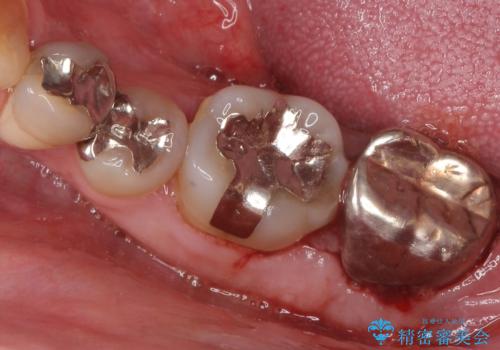

- 全顎的な重度歯周病の患者様です。

骨吸収の進行している左下臼歯部に、再生療法(骨を増やす手術))を行いました。